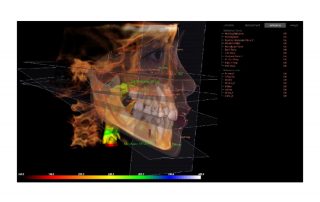

i-CAT FLX V17

Designed to accommodate the widest range of clinical applications, the V17 is the most flexible of the V-Series options. This unit has a maximum and scalable FOV of up to 23 cm x 17 cm. The V17 is used most often by orthodontists, oral maxillofacial surgeons and oral radiologists.

i-CAT QuickScan and QuickScan+ protocols allow you to take complete 3D images at a radiation dose comparable to a 2D panoramic image. The flexibility in scalable scan sizes further allows you to limit the dose to the patient.